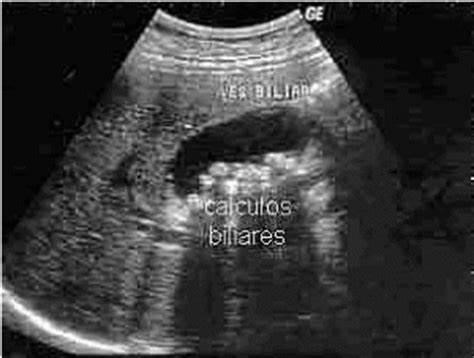

Os cálculos biliares, colelitíase, ou simplesmente “pedras da vesícula biliar” acometem cerca de 20% da população [1] e são decorrentes da cristalização de componentes da bile, predominantemente o colesterol (80%) e dos pigmentos da bile (20%).

O diagnóstico da colelitíase é baseado na história clínica e confirmada principalmente através da ultrassonografia abdominal, que tem alta acurácia. Exames como tomografia e ressonância nuclear magnética podem ser utilizados quando existe suspeita de complicações, como as descritas anteriormente, mas não configuram a melhor opção para o diagnóstico. Algumas pessoas consideram que exames mais sofisticados possuem maior acurácia, mas é importante a compreensão de que cada exame possui uma especificidade e sensibilidade distintos para diferentes diagnósticos. E, no caso da colelitíase, a ultrassonografia é um dos métodos de melhor acurácia.